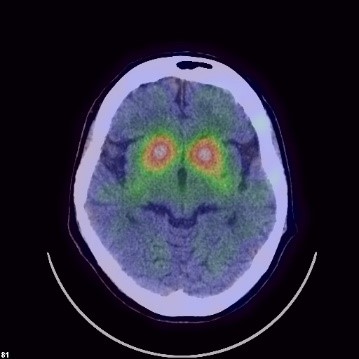

DATシンチ

この検査は、脳にある黒質線条体のドパミン神経の状態を視覚的にも把握できる検査です。この検査で使用する放射性医薬品は123I-ioflupane(商品名:ダットスキャン)で、前述のドパミン神経の終末部に高発現するドパミントランスポーター(以下DAT)に対し高い親和性を示すためSPECT画像ではDATの脳内分布を評価することができます。当院では投与後3時間後に30分程度の撮像を行います。パーキンソニズムをきたす疾患の鑑別に有用です。